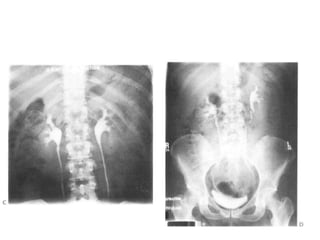

Post contrast IVU films.

• (A) Immediate,

• (B) 5 min,

• (C) 15 min film with

compression producing

calyceal distension;

• (D) full length release;

• (E) full length post

micturition.

Post contrast IVUfilms. • (A) Immediate, • (B) 5 min, • (C) 15 min film with compression producing calyceal distension; • (D) full length release; • (E) full length post micturition.